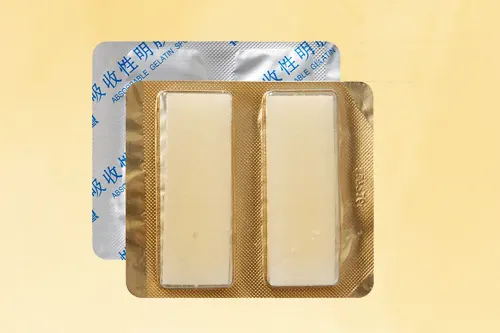

可吸收止血流体明胶临床试验注册案例

三类器械注册